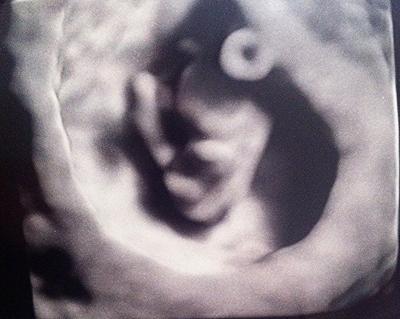

Vorerst der Hinweis das mein FA verrückt nach Ultraschall ist...schon bei meiner ersten und zweiten Schwangerschaft machte er bei jedem Treffen Ultraschall und seit er 3D in der Praxis hat auch das...ich bin darüber natürlich sehr glücklich...wenn hier Mädels aus dresden sind kann ich euch den gern empfehlen. Und hier mein kleiner Baby-Floh...

Bild zu 3D bei 8+3 - Forum für März - Mamis

Das ist ja toll man kann ja schon richtig viel erkennen! Herzlichen Glückwunsch und weiterhin alles Gute!